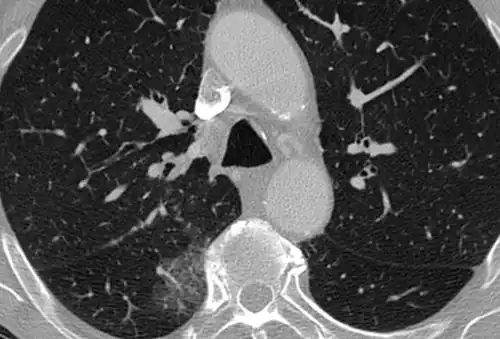

CT showing diffuse ground-glass opacities in periphery of both lungs in patient with COVID-19.

CT image in patient with COVID-19 showing bilateral ground-glass opacities at the periphery of both lungs.

Several studies have described a pattern among initial, intermediate, and hospital discharge imaging findings in the disease course of COVID-19. Most commonly, initial CT imaging reveals bilateral GGOs at the periphery of the lungs. During initial stages, this is most often found in the lower lobes, although involvement of the upper lobes and right middle lobe has also been reported early in the disease course.[16][18] This is in contrast to the two similar coronaviruses, SARS and MERS, which more commonly involve only one lung on initial imaging.[19][20] As the COVID-19 infection progresses, GGOs typically become more diffuse and often progress to consolidation.[11][18] This is sometimes accompanied by the development of a crazy paving pattern and interlobular septal thickening.[18] In many cases the most severe pulmonary CT abnormalities occurred within 2 weeks after symptoms began.[17] At this point, many individuals begin showing resolution of consolidation and GGOs as symptoms improve. However, some patients have worsening symptoms and imaging findings, with further increase in septal thickening, GGOs, and consolidation. These patients may develop lung "white-out" with progression to acute respiratory distress syndrome (ARDS) requiring treatment escalation.[17][21]